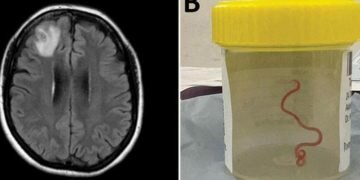

Aug 29 (BBC) – In a world first, scientists say that an 8cm (3in) worm has been found alive in the brain of an Australian woman.

The “string-like structure” was pulled from the England-born patient’s damaged frontal lobe tissue during surgery in Canberra last year.

“Everyone [in] that operating theatre got the shock of their life when [the surgeon] took some forceps to pick up an abnormality and the abnormality turned out to be a wriggling, live 8cm light red worm,” said Sanjaya Senanayake, an infectious diseases doctor at Canberra Hospital.

The patient was admitted to hospital in late January 2021. A scan later revealed “an atypical lesion within the right frontal lobe of the brain”. The cause of her condition was only revealed by a surgeon’s knife during a biopsy in June 2022.